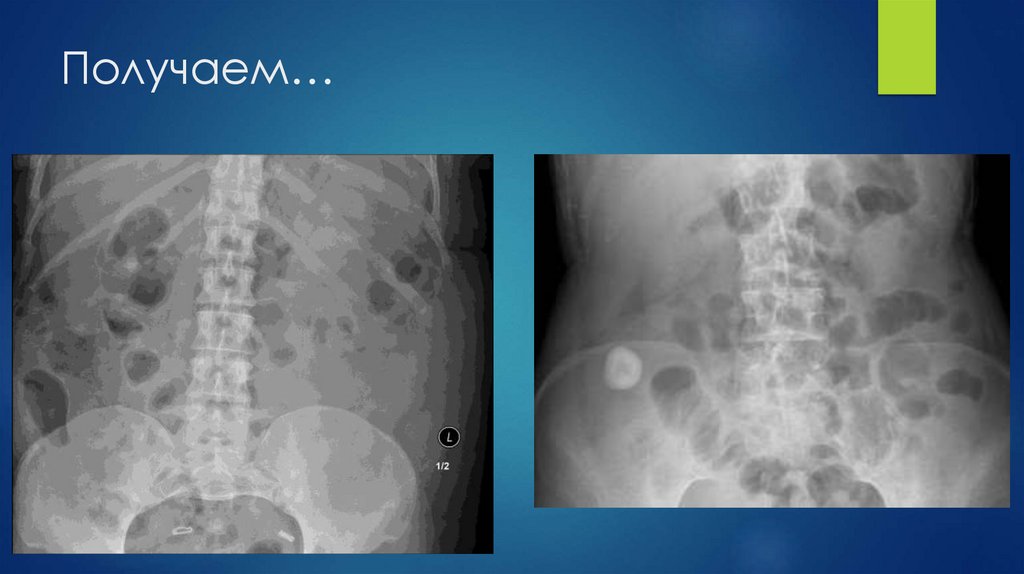

36. Получаем…

Получаем…